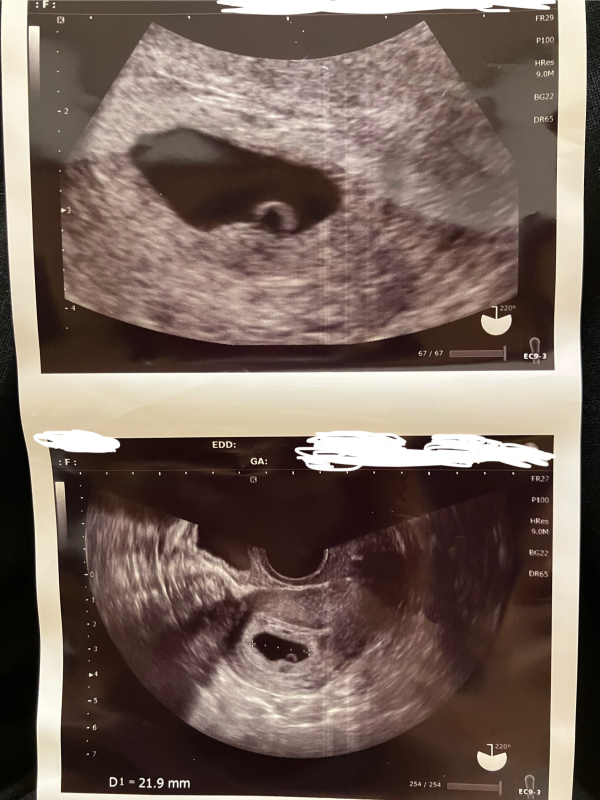

妊娠5w5dのエコーで21.9mmの胎嚢、および卵黄嚢が確認できました。しかし、胎芽は確認できませんでした。次回の診察は11日後とかなり先です。

胎嚢は週数をふまえると大きめだと思います。にも関わらず、胎芽が確認されませんでした。今の状況は、稽留流産の可能性が高いということでしょうか。

通常ですと、7週以上が経過しても胎嚢内に胎芽が見えない場合は、胎芽が正常に発育せず、流産の可能性が高まるとされています。匿名希望さんの場合ですと、まだ5週ということであれば、もう少し経過を見て、胎芽が見えてくるようになれば、問題ないことも多いですよ。お写真からですと、なかなかはっきりとは明言できませんが、胎嚢がしっかり大きくなっているようですので、あまり悲観なさらなくてもいいように思いますよ。今はご不安な気持ちでいっぱいかと思いますが、医師ともしっかりとコミュニケーションを取りながら、赤ちゃんの生きる力を信じてあげてくださいね。